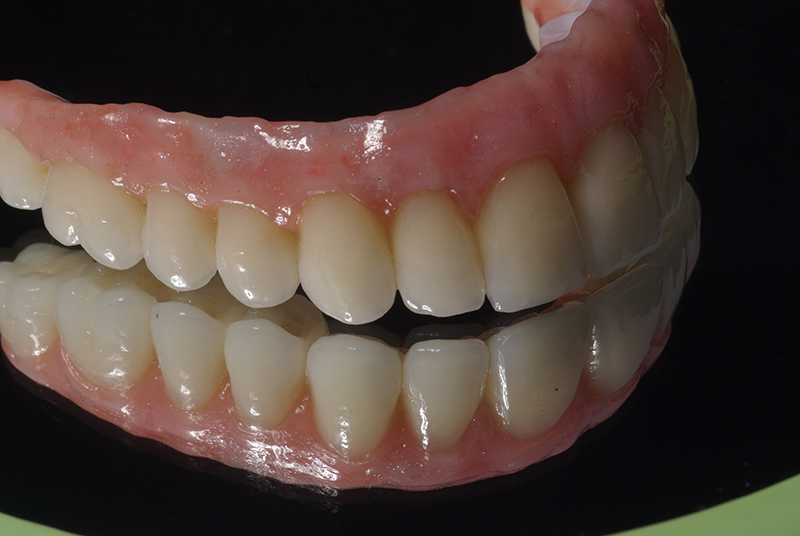

Utilizamos a tecnologia CAD CAM, um sistema avançado que possibilita a confecção precisa das próteses dentárias diretamente sobre os implantes. Esse método inovador garante um ajuste perfeito, um resultado estético superior e proporciona muito mais conforto e durabilidade. Com o CAD CAM, nossos pacientes contam com um processo mais rápido e previsível para alcançar o sorriso desejado.